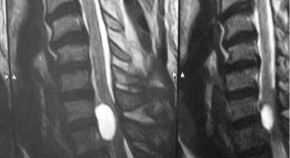

Spinal cord ischaemia is a rare complication following the gluteal injection of Benzathine benzylpenicillin. The hypothesis is embolization of the Penicillin products retrogradely through the Superior gluteal artery and cause occlusion of the vasculature that supply the spinal cord. This article includes literature review of the hypothesis behind the Spinal cord ischaemia and highlights the previous cases reported.